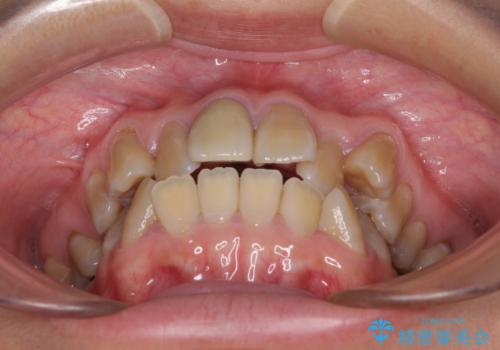

- 八重歯や前歯のデコボコを気にして来院された患者様です。

歯列が前方に傾斜しており、デコボコが強かったため、上下左右第一小臼歯4歯を抜去し、ワイヤー装置による矯正治療を行うこととしました。

上下の正中がずれていましたが、抜歯矯正であったので、極力正中位置を合わせるように治療を進めて行きました。

顎間ゴムの使用などにより、正中位置を改善することができました。